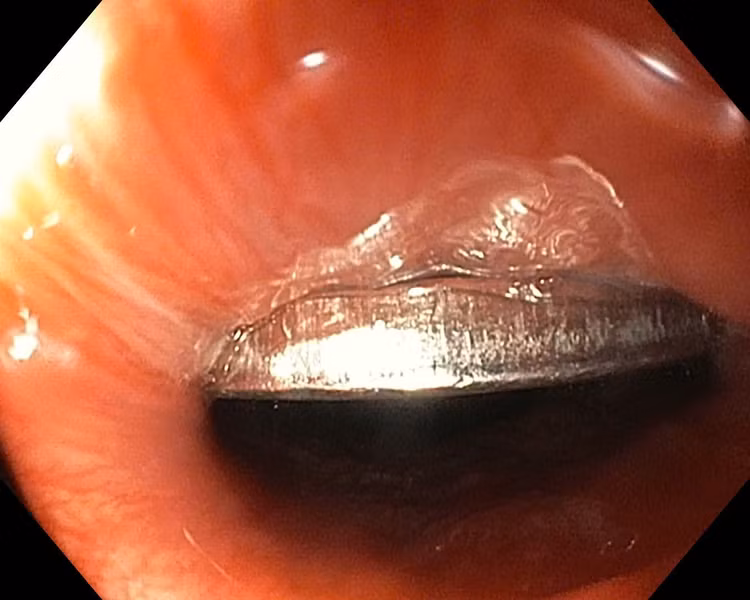

Dị vật đồng xu trong thực quản bệnh nhi - Ảnh BVCC

Ngay sau đó, bệnh nhi được chuyển đến Khoa Nội soi để thực hiện thủ thuật. Ê-kíp bác sĩ tiến hành nội soi dạ dày có gây mê, sử dụng dụng cụ chuyên dụng để tiếp cận và gắp dị vật ra ngoài. Sau khoảng thời gian ngắn, chiếc đồng xu đường kính 20mm đã được lấy ra an toàn.

Kiểm tra niêm mạc dạ dày – thực quản cho thấy không có tổn thương hay chảy máu. Bé tỉnh táo, sức khỏe ổn định và được xuất viện ngay trong đêm.